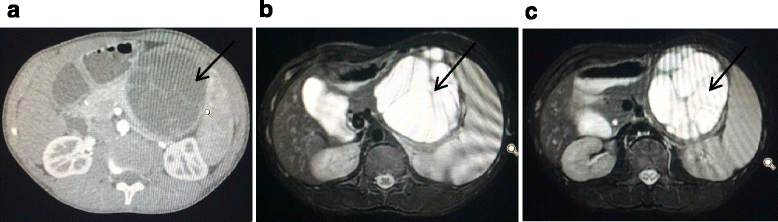

Case presentation: We describe the case of a 15-year-old boy, a Chinese national, who was diagnosed as having a pancreatic desmoid-type fibromatosis. He was a healthy individual who was incidentally diagnosed with an abdominal mass. His chief complaints were mild generalized abdominal pain for 1 week, nausea, vomiting, and a low-grade fever. An enhanced computed tomography scan of his abdomen showed a large cystic mass in the anterior surface of the body of his pancreas. He underwent a radical resection of the pancreatic mass, partial pancreatectomy, splenectomy, segmental resection of transverse colon and distal jejunum, and subsequently a one-stage jejunojejunostomy and colonic anastomosis. Postoperatively, he was diagnosed as having a desmoid-type fibromatosis of the pancreas by pathological and immunohistochemical studies.